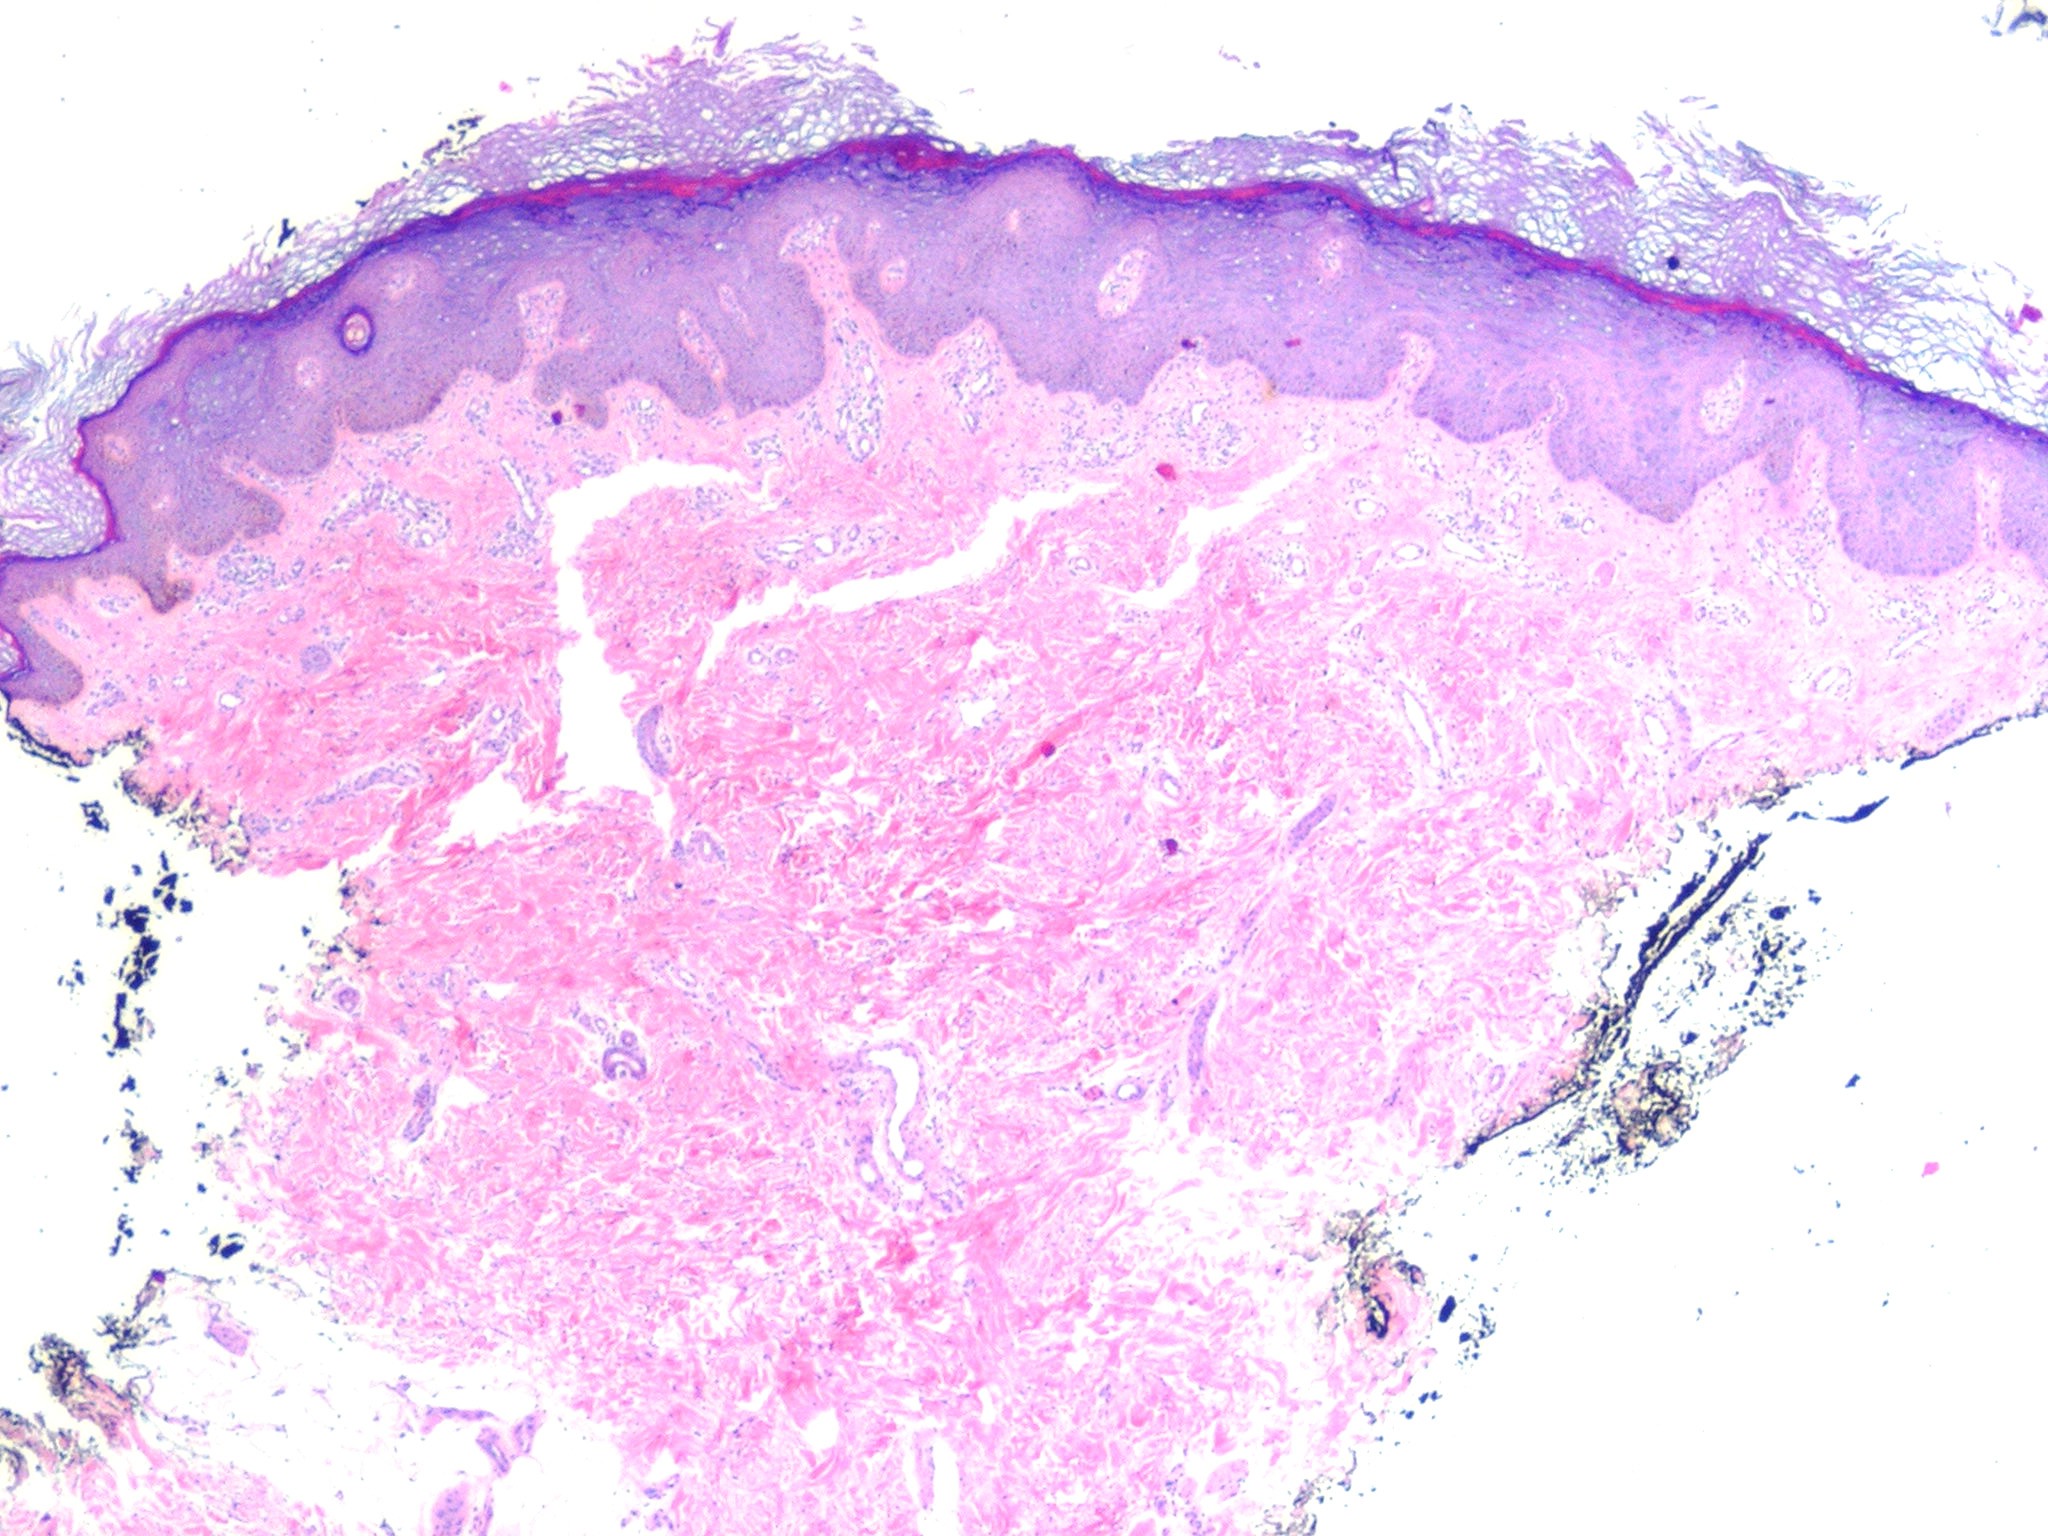

Epidermodysplasia Verruciformis =عسر تصنع البشرة الثؤلولي